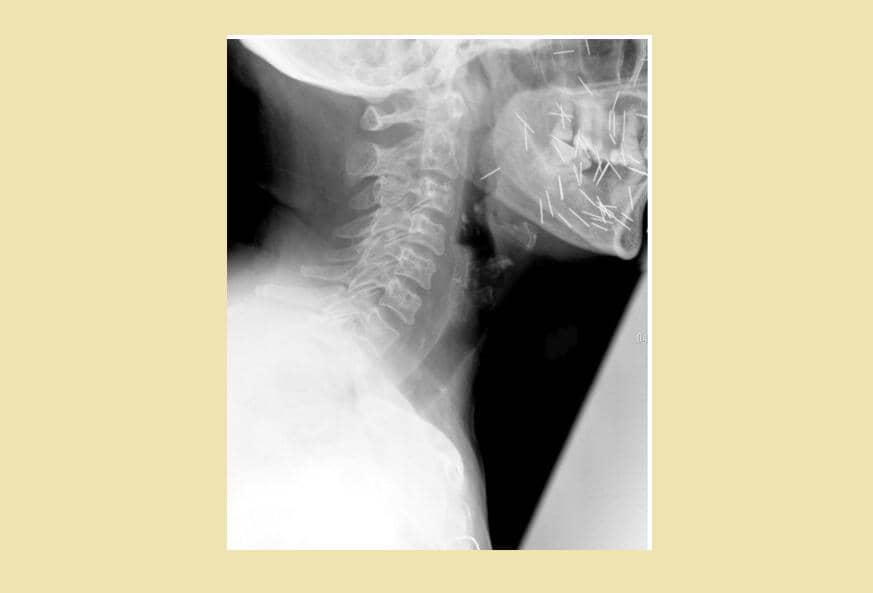

1. Ratusan susuk terlihat jelas lewat hasil foto sinar-X

Dalam unggahannya itu, Tasqia menuliskan bahwa ia sedang menangani seorang pasien berusia 55 tahun yang ingin melakukan X-ray atau sinar-X. Tak disangka, hasil foto sinar-X pasien tersebut memperlihatkan ratusan atau bahkan ribuan benda asing berbentuk seperti jarum yang bersarang pada tubuh pasiennya itu. Tasqia pun menyebut benda tersebut sebagai susuk. Sangking banyaknya, Tasqia pun tak tahu pasti berapa jumlah susuk yang ada pada bagian tubuh pasiennya itu.

"Pasien wanita, usia 55 tahun mau di X-ray. Nah kalo ini susuknya ada berapa? Itung sendiri deh ya :)," tulis Tasqia.

5. Umumnya ditemukan di sekitar kepala

Ketika ditanya biasanya susuk banyak ditemukan di area tubuh yang mana, Tasqia menjawab bahwa susuk bisa dimasukkan di mana saja. Namun, biasanya banyak ditemukan di sekitar kepala dan sisanya ada sekitar area kaki hingga payudara.

"LMAOOOO yess bisa dimana ajaaa cuma emang umumnya di daerah kepala, sisanya bisa di kaki tangan, perut, dada, payudara, dll," tulisnya.